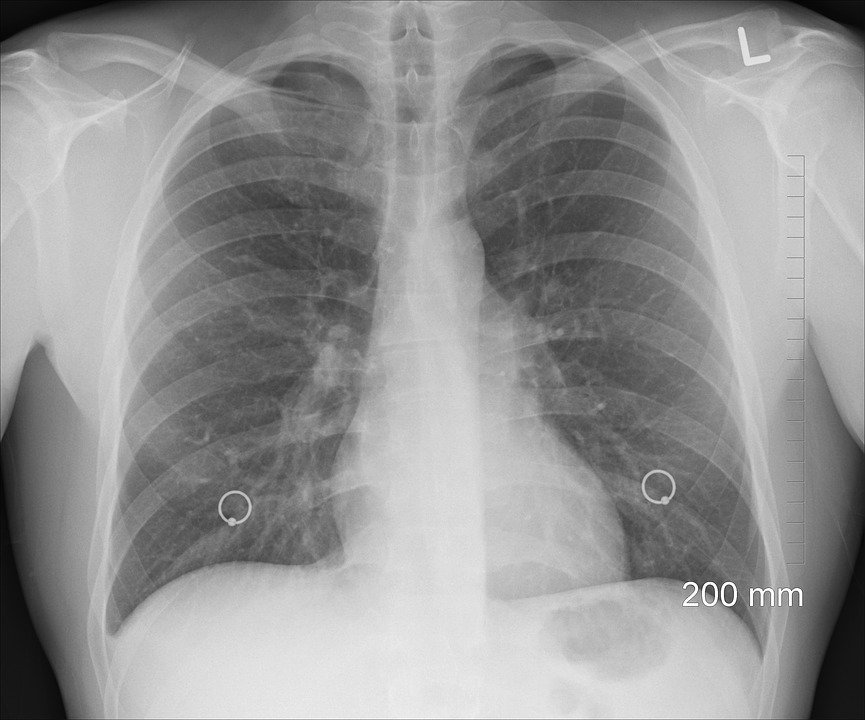

A recent study in the journal Cancer Discovery found that inhalation of harmful microbes can contribute to advanced stage lung cancer in adults. Long-term use of face masks may help breed these dangerous pathogens.

Microbiologists agree that frequent mask wearing creates a moist environment in which microbes are allowed to grow and proliferate before entering the lungs. Those foreign microbes then travel down the trachea and into two tubes called the bronchi until they reach small air sacks covered in blood vessels called alveoli.

While analyzing lung microbes of 83 untreated adults with lung cancer, the research team discovered that colonies of Veillonella, Prevotella, and Streptococcus bacteria, which may be cultivated through prolonged mask wearing, are all found in larger quantities in patients with advanced stage lung cancer than in earlier stages. The presence of these bacterial cultures is also associated with a lower chance of survival and increased tumor growth regardless of the stage.

Additionally, research into the cultivation of Veillonella bacteria in the lungs of mice found that the presence of such bacteria leads to the emergence of immune suppressing cells as well as inflammatory ones such as cytokine IL-17.